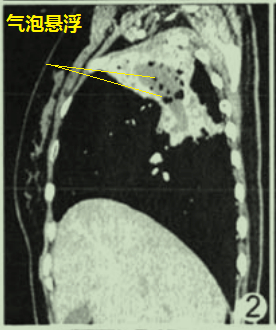

肺部空洞悬浮气泡征(图2),简单的说就是反常的存在,不把牛顿万有引力放在眼里(从表面上看):气体的分布与重力无关,不形成气液平,空气悬浮在液体里面。

图2 肺部空洞悬浮气泡征

图2 肺部空洞悬浮气泡征这个患者的病理是什么呢?

揭晓答案:放线菌感染(图3),空洞悬浮气泡征高度提示肺部放线菌病。

图3 放线菌感染图4也是肺部空洞悬浮气泡征,最终诊断也是肺部放线菌病。

图4 肺部空洞悬浮气泡征为什么肺放线菌病空洞内的空气会违反牛顿万有引力呢?有学者推测,对于肺放线菌病,空洞内低密度无强化的物质,其实是坏死组织+大量放线菌+硫磺颗粒,流动性差;空洞内的气体密度影,可能是含硫磺颗粒、放线菌的微脓肿,或是残存的扩张支气管。由此可见,空洞内的液体难以流动,气体也不容易流动,所以不会形成气液平。

比如,我们喝水,胃部可以形成气液平,但是吃饭则胃部难以形成气液平(图5)。

图5 CT影像

图5 CT影像3